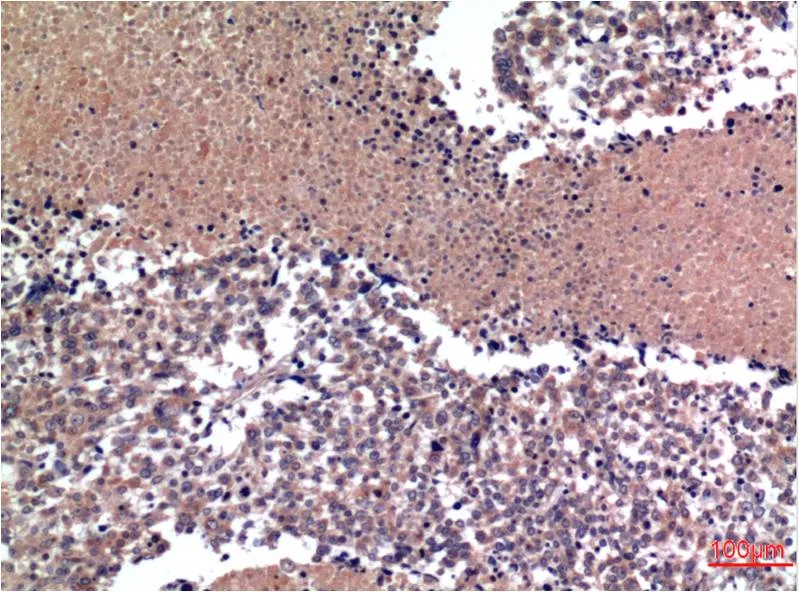

Cyclin B1 (1B3) Mouse Monoclonal Antibody

Cat: AMM00754